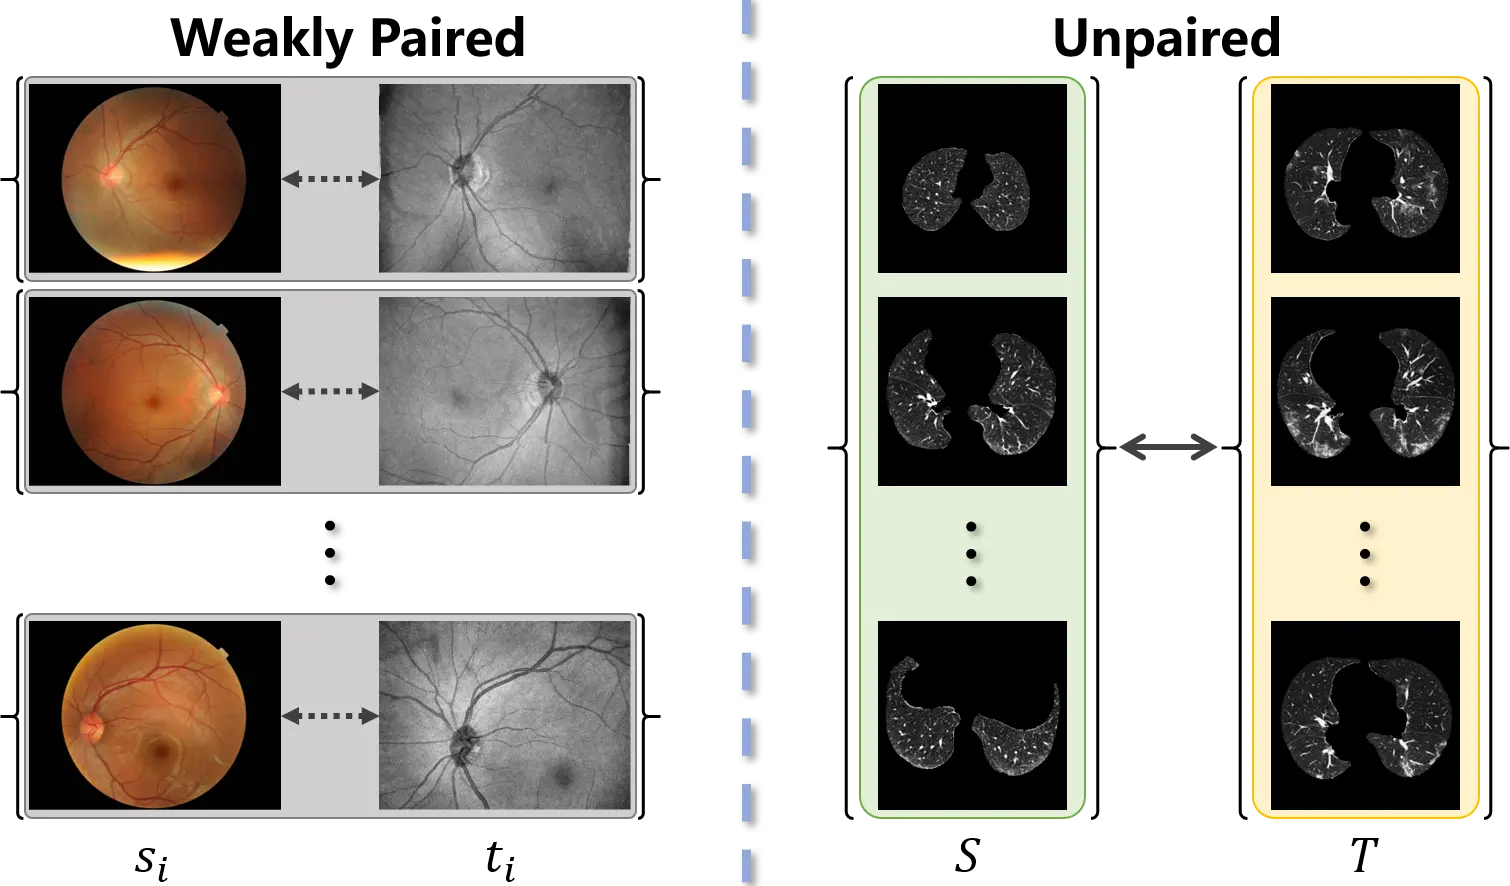

The acquisition of training data for image-to-image translation is a formidable task in medical scenarios. Most of the applications based on image-to-image translation follow one of two fundamental frameworks, namely pix2pix[5] and CycleGAN[6], depending on whether the training data are paired or unpaired. As pix2pix is trained under supervision, paired input-output samples are necessary for its implementation. However, such a training set is hard to obtain in practice. Many factors, such as divergence between individuals, changes with time, and differences in imaging mechanisms, will lead to misalignment of the images. Consequently, as shown in Figure 1, weakly paired data (pairwise captured and sharing an overlapping field of view) and unpaired data (independently collected) are more common in medical images. To mitigate the limitation of image-to-image translation and make full use of available data, CycleGAN was proposed to translate an image from a source domain to a target domain in the absence of paired examples. Although weakly paired and unpaired data have been successfully utilized to perform image-to-image translation, the distribution bias between the source and target samples has not been overcome.

Figure 1. Weakly paired dataset (left) consists of training examples